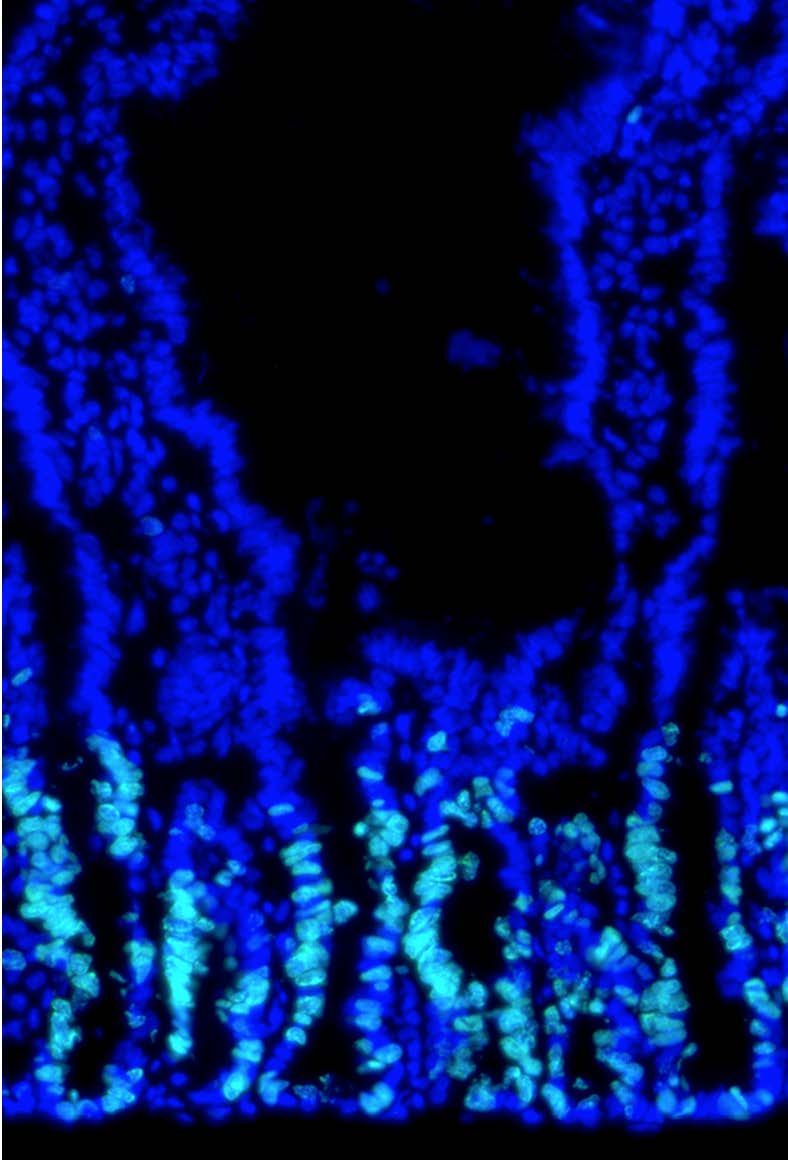

Tontonoz Lab/UCLA

Stem cells multiplying in a mouse intestine.